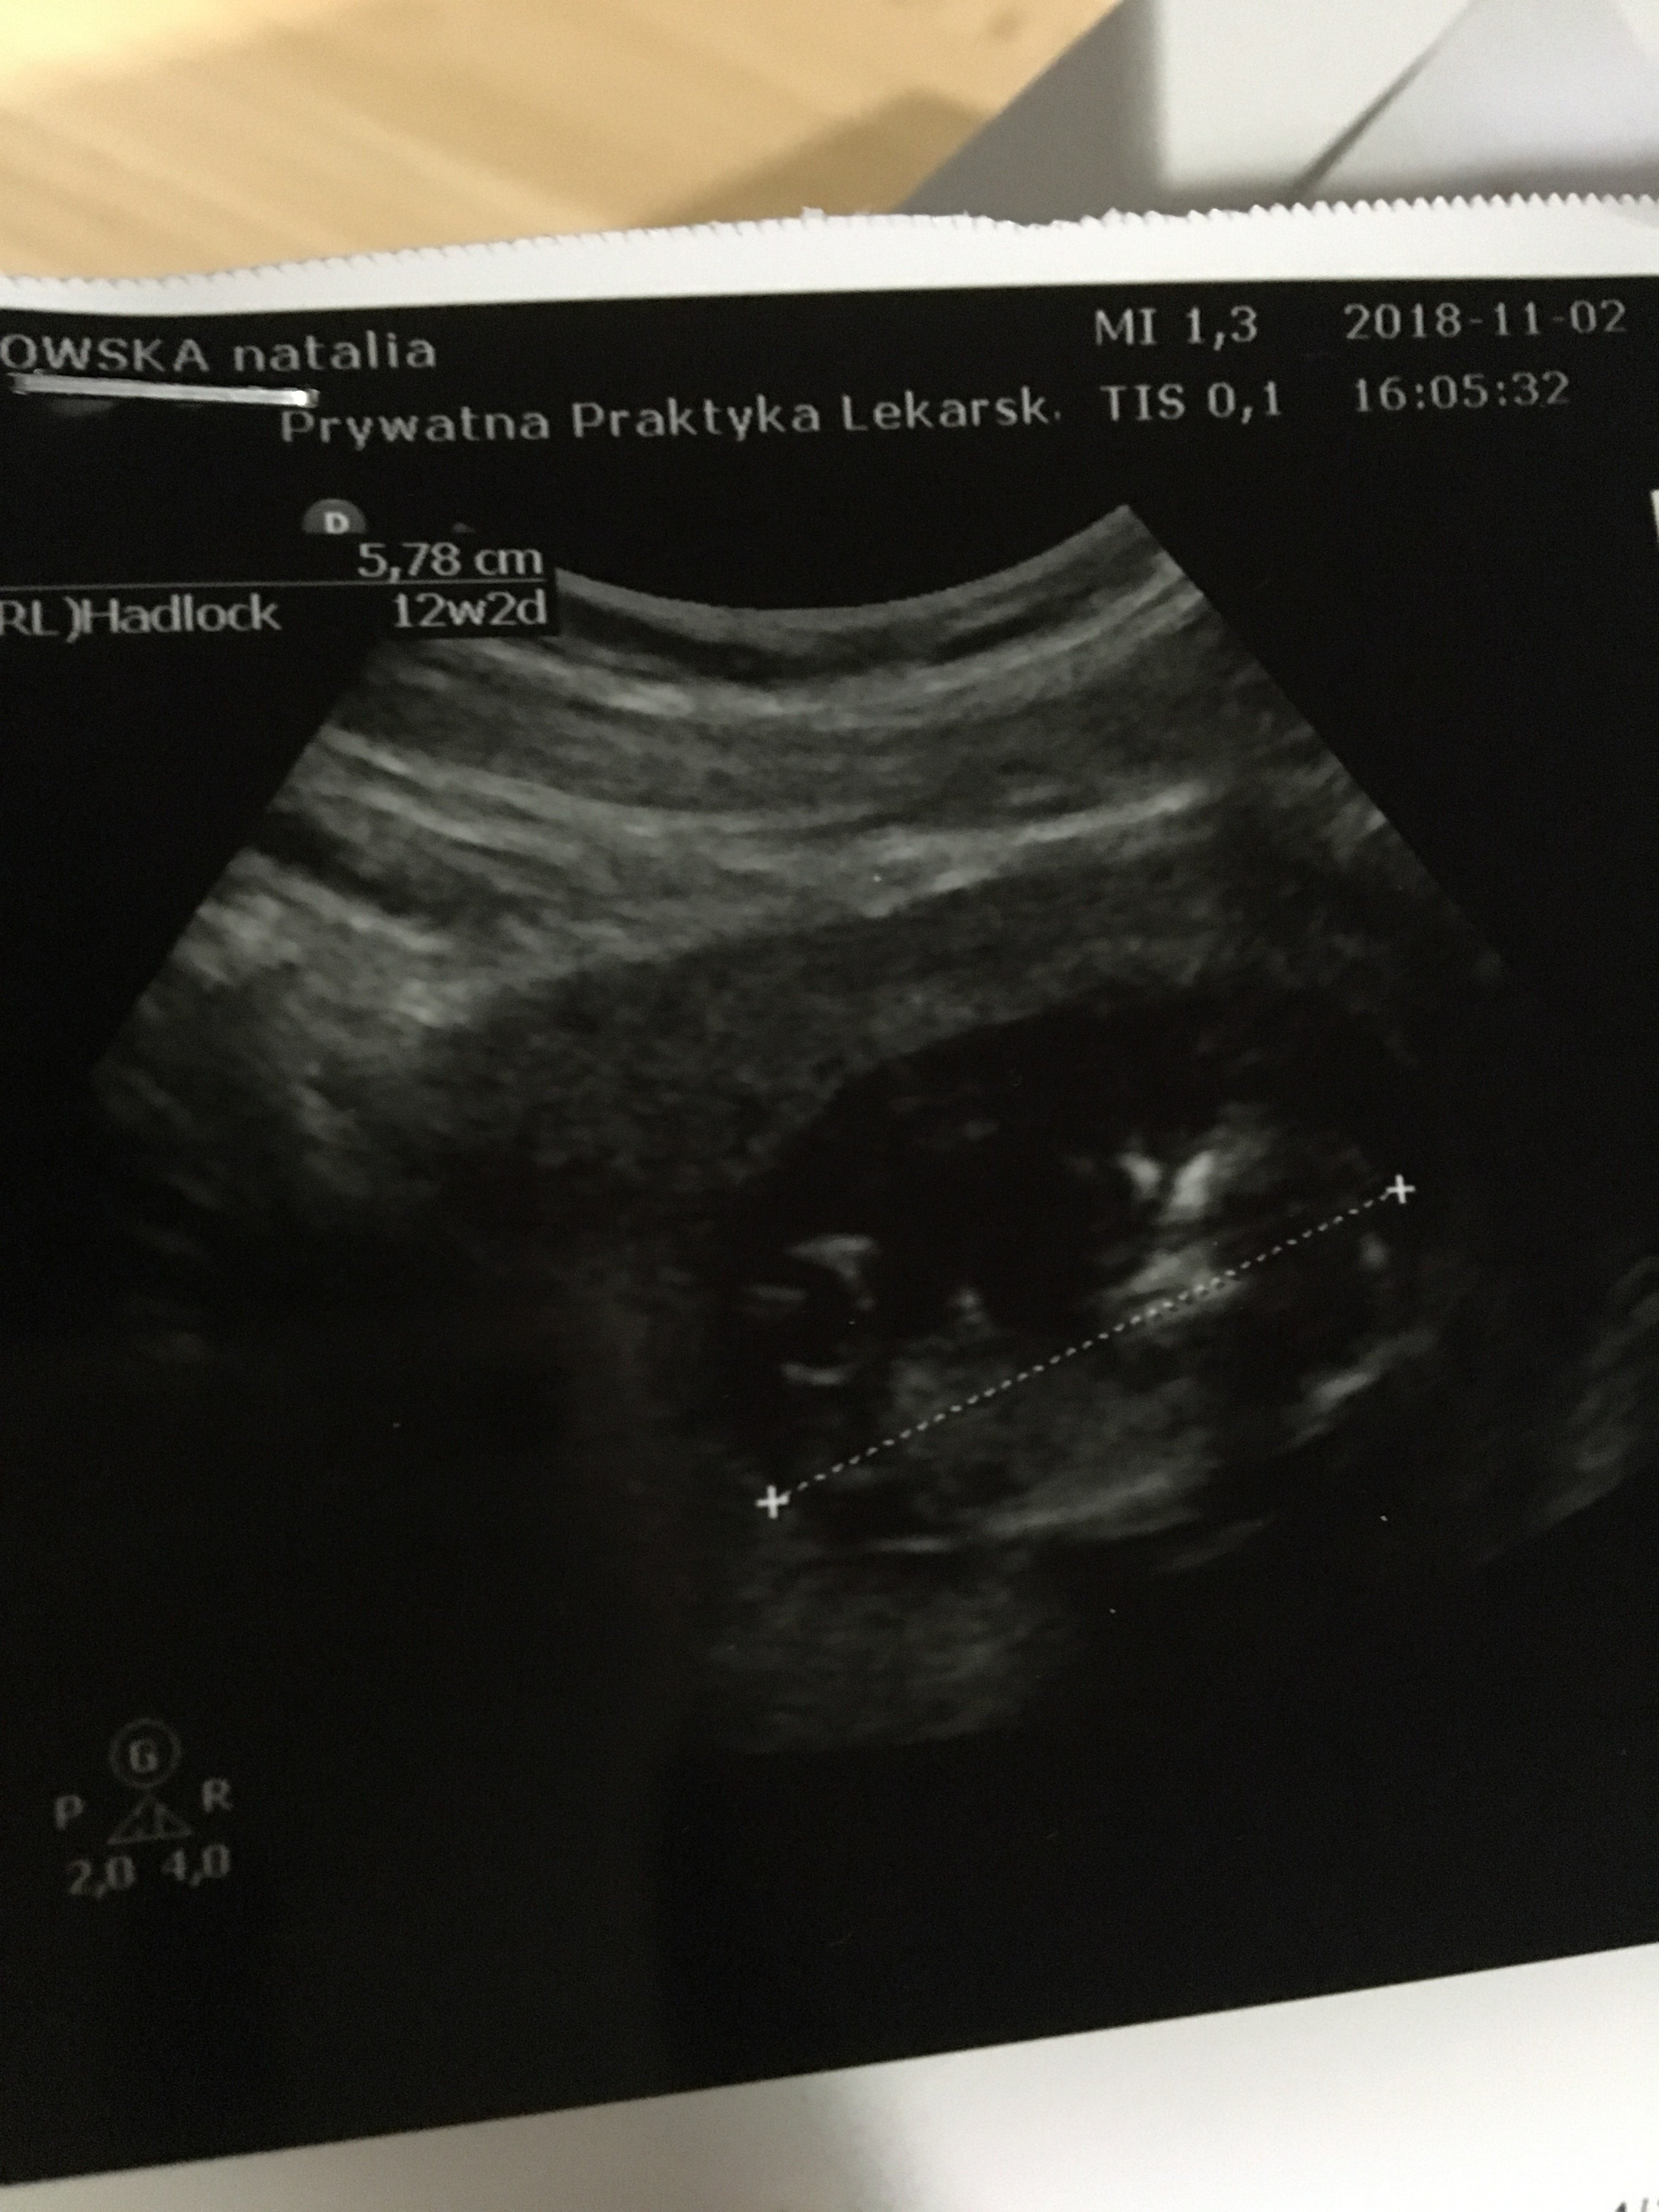

Witam w 19 tygodniu ciąży dowiedziałam się ze będę miała dziewczynkę w 20 tyg okazało się jednak , że to chłopak. Sama już nie wiem bo na jednym usg widać na pewno dziewuche a na drugim chłopca. Może to pempowina ?? Może ktoś mi pomoże rozwiązać ta zagadkę

no nic , zobaczymy na kolejnym USG. To doswiadczona Pani wiec chyba wie co mówi a ja ogladam zdjęcia pod każdym kątem i szukam śladów kobiecych